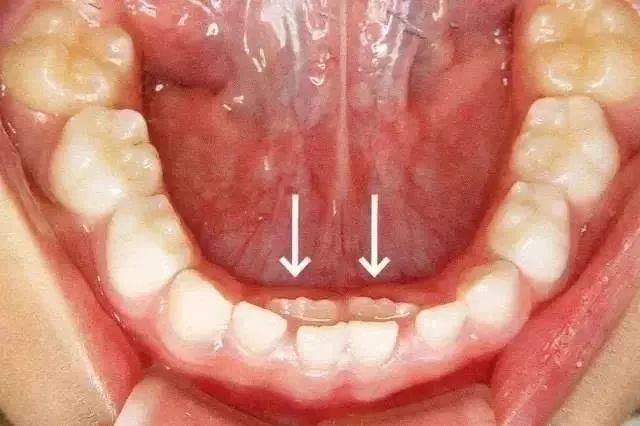

当依据经历,觉得孩子该换牙时,乳牙迟迟不掉,不少新爸爸新妈妈难免严峻。乳牙停留不掉落是一件麻烦事,是咱们要防止的问题。图承继恒牙已萌出,乳牙未掉落(箭头指示承继恒牙)“双排牙的问题现在在临床上很常见,咱们碰到每10个小朋友至少有5个存在,有些好一点的乳牙现已松动,而有些凶猛的乳牙文风不动,只能经过外力拔